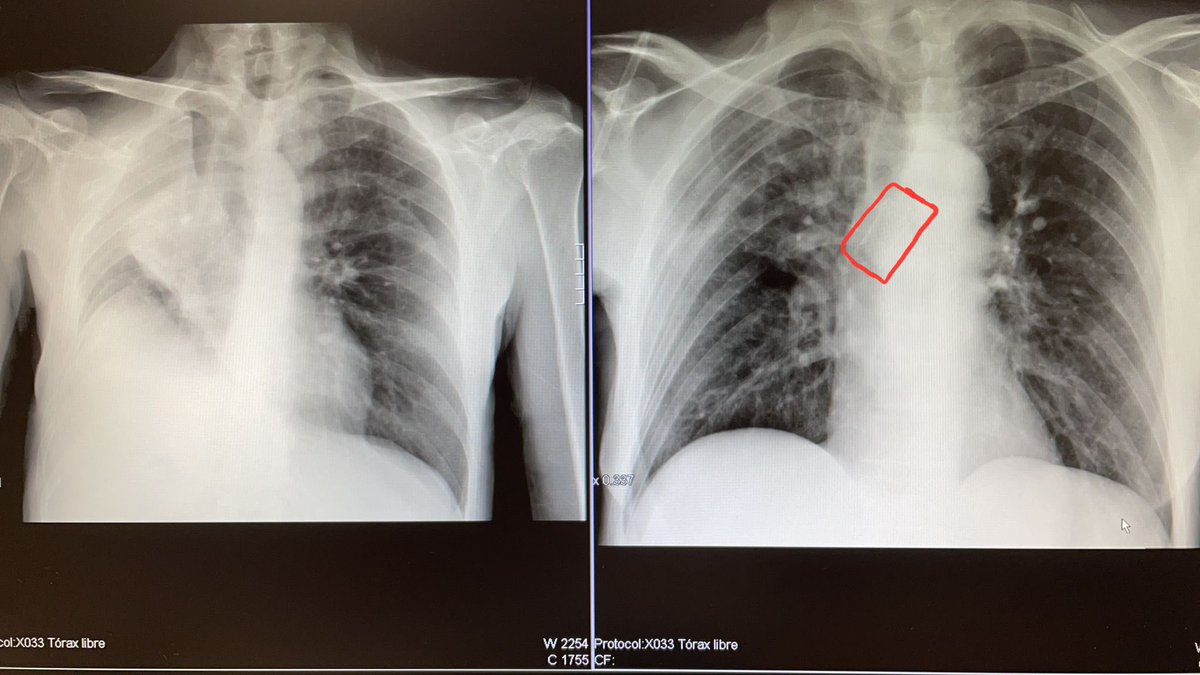

Porque #notodoescovid en la neumologia. Aqui vemos el antes y despues en la Rx y EN LA VIDA de un paciente con @cancerdepulmon tras una prótesis en bronquio ppal dcho Seguimos creciendo y avanzando en Neumología HGU. Santa Lucía Cartagena y AnestesiaR del @Area2Cartagena